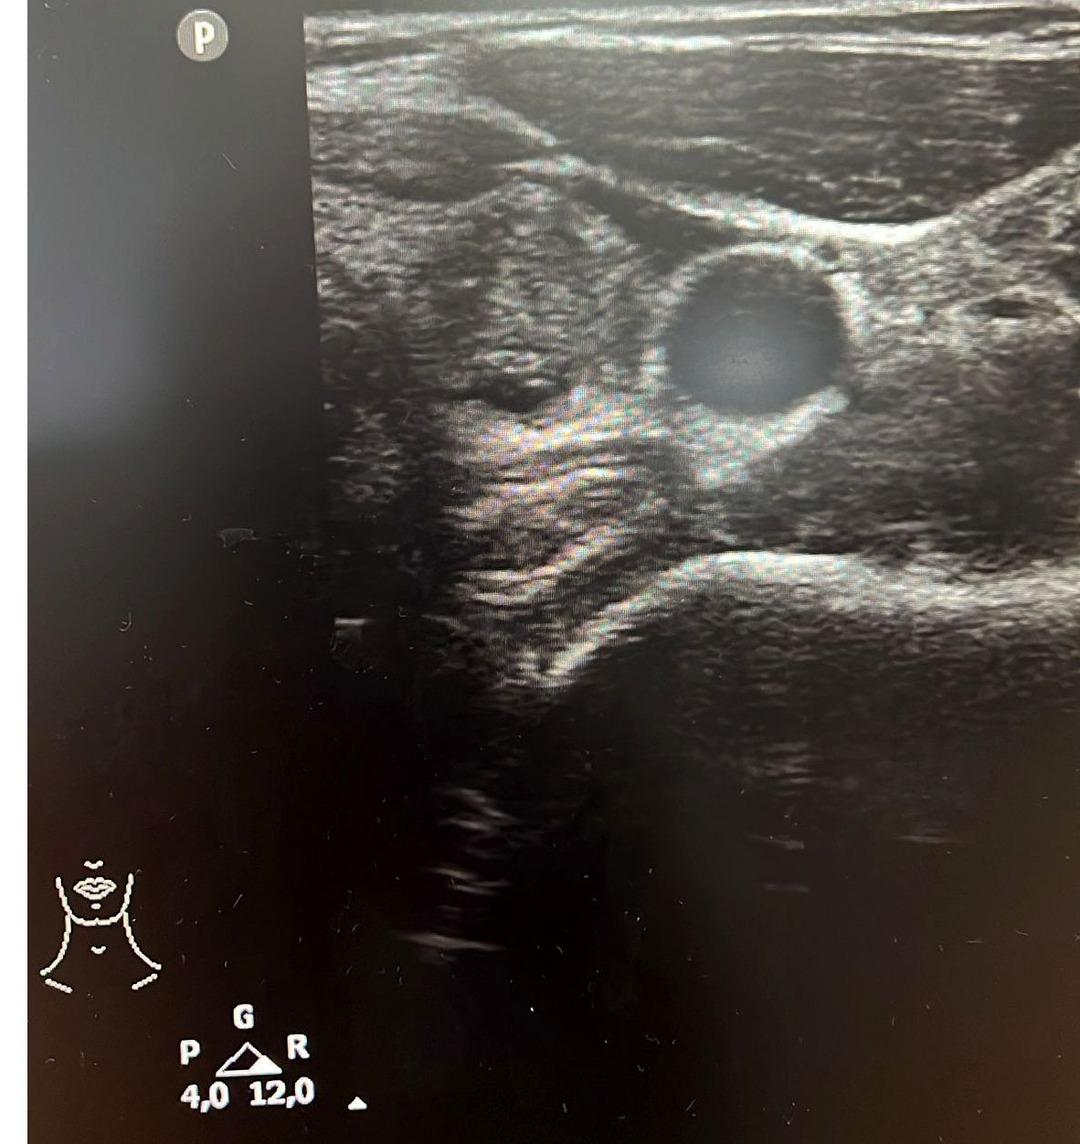

Tiroit nodülü tespitinde farkındalığın artığını ifade eden Dr. Demir, "Nodül tespitindeki farkındalığımız arttı. Tiroit ultrasonu kullanıyor olmamız da bu artışa etken oldu. 'Bası bulgusu' ile dokunarak muayene ettiğimizde; mevcut olan nodüllerin yaklaşık yüzde 20’sini tespit edebiliyoruz. Nodüllerin birçoğunun özelliklerini ve boyutlarını ise tiroit ultrasonu ile tespit ediyoruz. Son dönemlerde vakalarda artış var. Bazen hiçbir semptomu olmayan hastalarda da tiroit nodülleri tespit ediyoruz. Nodülleri özelliklerine göre değerlendirerek gerekli hastalardan biyopsi alıyoruz. İyi ya kötü huylu nodüle göre tedavi uyguluyoruz. Nodülü belli aralıklarla takip ediyoruz. Tiroit nodüllerinin yüzde 10 ila 20 kadarı kötü huylu olabiliyor. Birçok kanser türü erkek hastalarda fazla görülürken, özellikle tiroit kanseri sıklığı kadın hastalarımızda daha yüksektir. Kadın hastalar daha sık muayeneye geliyor ve farkındalıkları daha yüksek" dedi.